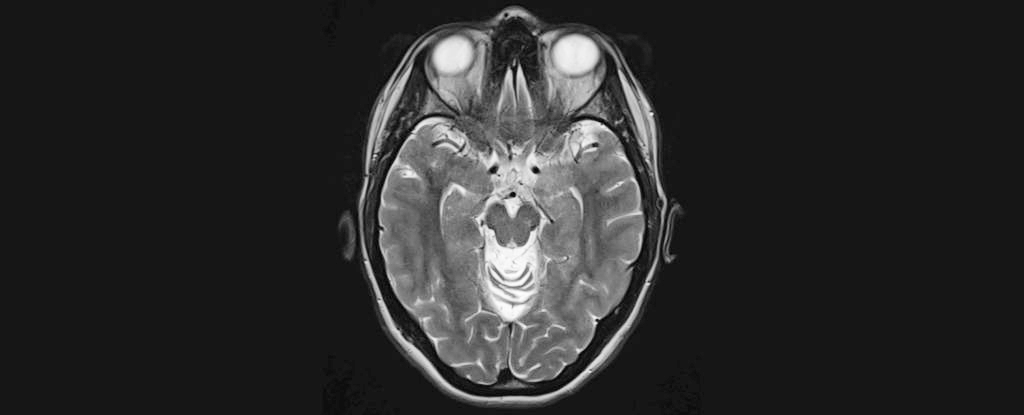

Researchers have developed a tool to predict the next five years of cognitive decline in Alzheimer's patients, offering hope for better prognosis and treatment planning. The model, based on MRI scans, biomarkers, and cognitive test scores, can help inform patients and caregivers about disease progression, although predictions can vary. The study, published in Neurology, aims to refine these models for more accurate future predictions.